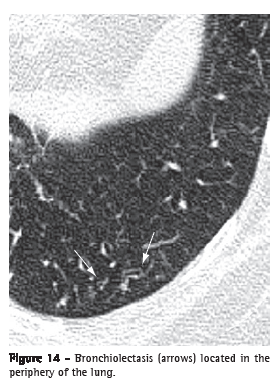

Bronchiolectasis (bronquiolectasia)

Bronchiolectasis refers to the dilatation of a bronchiole. It is analogous to bronchiectasis, but it affects an airway of much smaller diameter, identified in the periphery of the lung (Figure 14). Bronchiolectasis manifests as rounded or tubular structures, generally located in the periphery of the lung, with thick walls or filled with secretion (see also Tree-in-bud pattern).(3,7) It can also be combined with other pulmonary opacities and to the distortion of the parenchyma in cases of fibrosis.